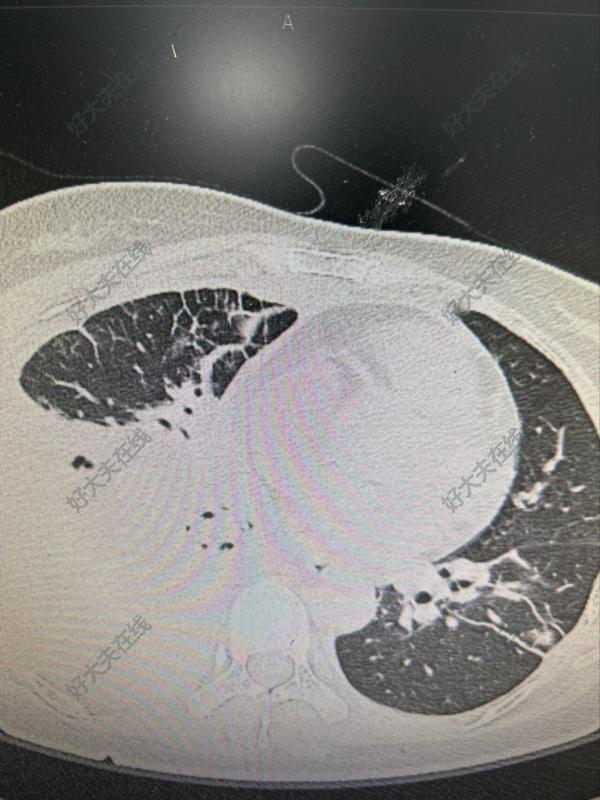

左肺下葉巨大肺膿腫

患者2024年3月無明顯誘因出現(xiàn)咳嗽咳痰,黃痰,偶有血絲,量少,伴發(fā)熱,最高39.4℃,伴左側(cè)胸痛,咳嗽時嚴重,輕度胸悶。1天前在當(dāng)?shù)蒯t(yī)院檢查胸部CT提示“左側(cè)肺膿腫伴炎癥”,轉(zhuǎn)來我院就診。入院后完善相關(guān)檢查結(jié)果檢查不得了,發(fā)現(xiàn)他患有嚴重的糖尿病,他以前不知道的。術(shù)前的感染指標都非常高。入院化驗檢查C反應(yīng)蛋白直接爆表,大于370mg/L;白細胞:20.3210^9/L術(shù)前超敏C反應(yīng)蛋白?術(shù)前影像:??出院后1周復(fù)查胸片?因為患者高齡65歲,病情比較復(fù)雜,既往有糖尿病史,既往從來沒有未降糖治療。入院的時候,患者一般狀況較差,有發(fā)熱,感染指標很重,身體虛弱,完全是一個負氮平衡的營養(yǎng)不良狀態(tài)。患者家屬同時去市內(nèi)多家醫(yī)院會診,不能提供住院治療。該患者術(shù)前經(jīng)過請院內(nèi)MDT多科室會診,在科室的討論下,制定了治療方案。術(shù)前給予有效抗炎治療,控制血糖,積極改善患者營養(yǎng)狀況。在科室討論后制定治療方案。由石磊副主任醫(yī)師團隊采用3D胸腔鏡單孔微創(chuàng)的治療方式,行3D單孔胸腔鏡下左肺下葉切除術(shù)。術(shù)后繼續(xù)給予抗炎治療,控制血糖,營養(yǎng)支持治療。術(shù)后經(jīng)過科室醫(yī)護團隊細致的治療,順利康復(fù)。出院后,患者家屬對胸外科的治療豎起了大拇指。家屬表示:“在家門口的醫(yī)院幫助我們解決了疑難病癥,我們對胸外科的治療非常滿意。